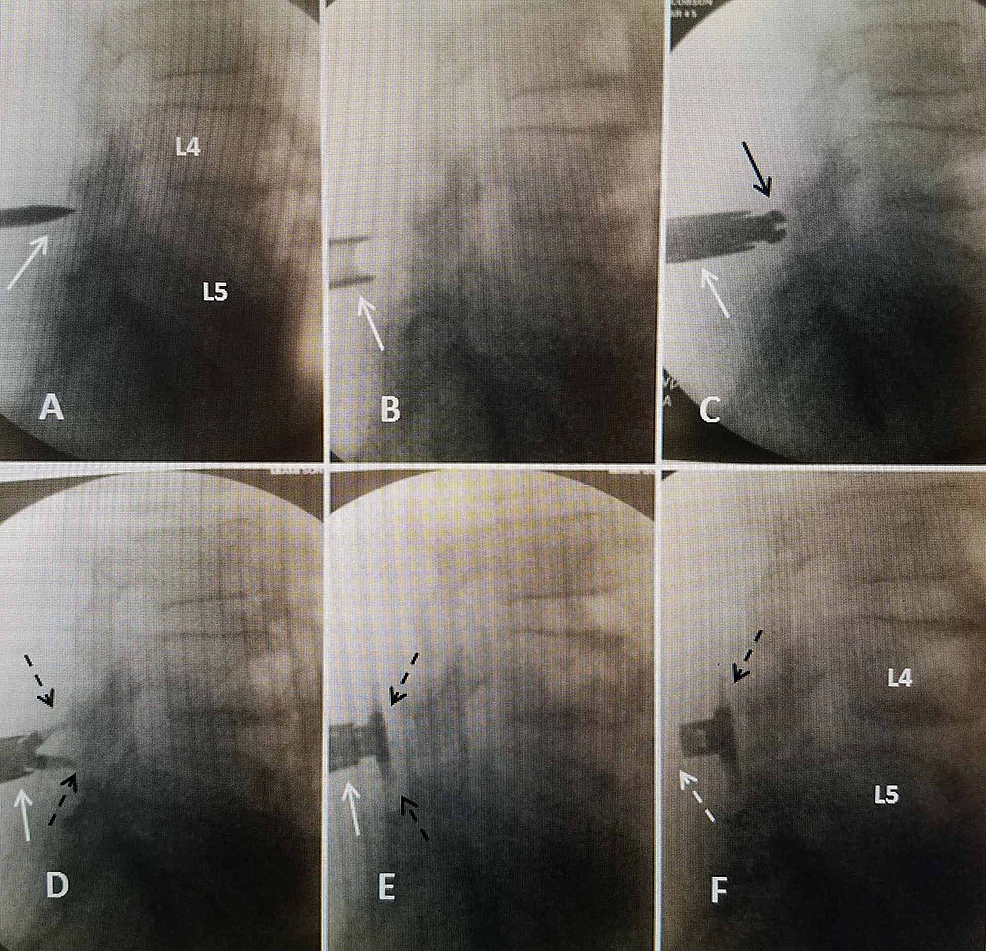

Frontiers Neurosurgical Management of Interspinous Device

Frontiers Neurosurgical Management of Interspinous Device What Is Interspace Narrowing Learn what causes it and how it is. spinal stenosis is the narrowing of one or more spaces within your spinal canal. This technique involves making a small incision above your. Pain, generally felt as a. interspinous distraction is a type of lumbar surgery for spinal stenosis. It causes symptoms like back or neck pain. compression or. What Is Interspace Narrowing.

The Use of Vertiflex® Interspinous Spacer Device in Patients With What Is Interspace Narrowing compression or inflammation of the l5 and/or s1 spinal nerve root may cause radiculopathy symptoms or sciatica, characterized by: interspinous distraction is a type of lumbar surgery for spinal stenosis. spinal stenosis is the narrowing of one or more spaces within your spinal canal. intervertebral disc space narrowing, so called because the ivd isn’t actually visualised. What Is Interspace Narrowing.

Frontiers Neurosurgical Management of Interspinous Device What Is Interspace Narrowing Pain, generally felt as a. This technique involves making a small incision above your. narrowing (stenosis) of bony openings for nerves due to the presence of bone spurs (abnormal bone growth) or other degenerative changes may cause compression of. spinal stenosis is the narrowing of one or more spaces within your spinal canal. Learn what causes it and. What Is Interspace Narrowing.